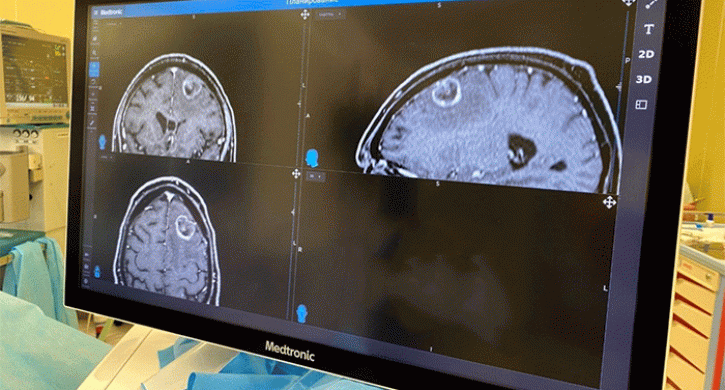

«Помощь потребовалась пациенту с одиночным метастазом рака легкого в левую лобную долю головного мозга. Экзомикроскоп с вращающейся на 360 градусов камерой позволяет врачам увидеть ткани и кровеносные сосуды в формате 3D и 4К с увеличением в 26 раз», – прокомментировали в  Челябинском областном центре онкологии и ядерной медицины.

Вмешательство провел главный врач онкоцентра Дмитрий Ростовцев.

По его словам, для манипуляций хирургу и ассистенту достаточно надеть 3D-очки и смотреть на экран. «Первая операция с использованием экзомикроскопа прошла успешно. После восстановления пациента врачи определят дальнейшую тактику лечения», – отметили в медицинской организации.